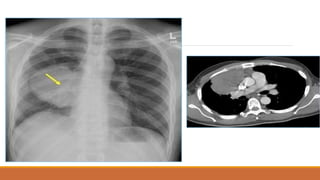

TDMP lượng ít

TDMP lượng vừa

TDMP lượng nhiều